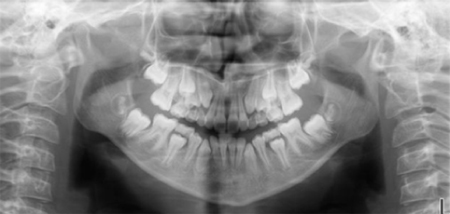

Ce dossier orthodontique est constitué de radiographies réalisées au cabinet, de moulages des dents, de photographies.

Radiographie panoramique